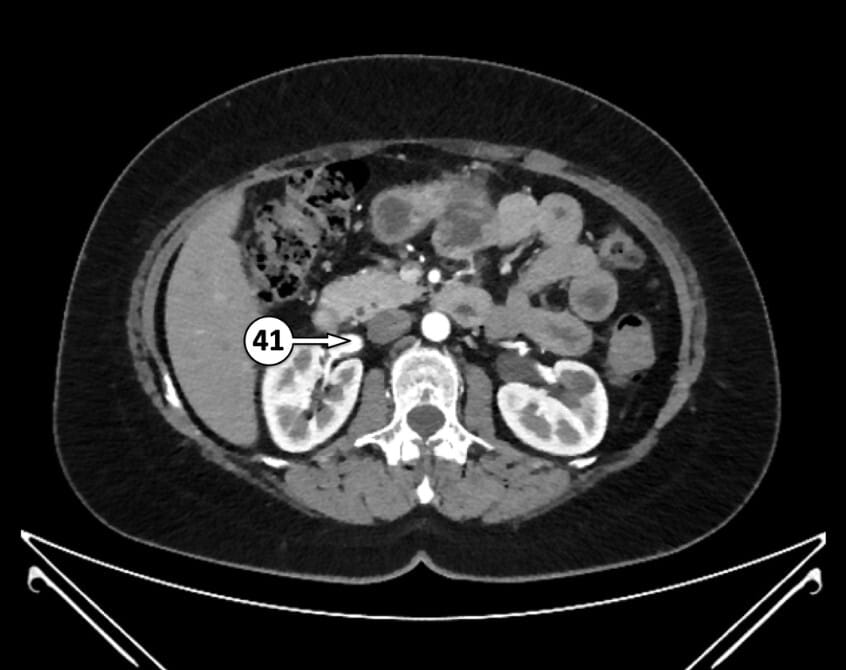

41. right renal vein